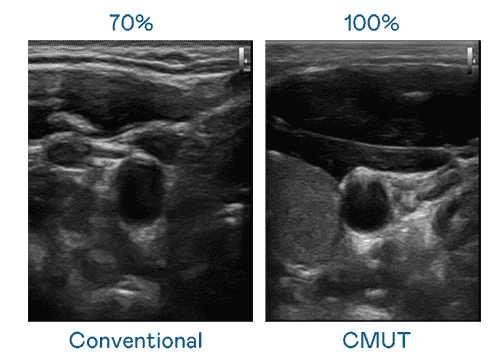

CMUT 技术是一种用电容式微机电元件来产生超音波讯号的技术。。。。与传统 PZT 压电式技术相比,,,,CMUT 频宽增加 30%,,,更宽频的超音波讯号让影像解析度大幅提升,,,,是实现高影像品质医疗超音波扫描、、、促进精准医疗发展的关键技术。。。

大频宽带来超清晰影像

超音波影像的解析度高低,,,,首先取决于探头能发出的讯号频宽。。。。JDB电子 CMUT 可提供高清晰的超音波讯号,,,提供高频宽、、高灵敏度、、影像纹理细节更高的超音波影像,,,协助医护人员缩短影像判读时间及利用精准的医疗影像进行诊断。。。。